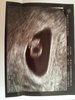

Jestem po pierwszym USG:) serduszko bije 156 uderzeń na minute, maleństwo ma 1,26cm, wszystko w jak najlepszym porządku:D

Załączniki

• IMG_20180820_184438.jpg

IMG_20180820_184438.jpg

50,7 KB · Wyświetleń: 253

• IMG_20180820_193057-1512x1368.jpg

IMG_20180820_193057-1512x1368.jpg

720,3 KB · Wyświetleń: 253